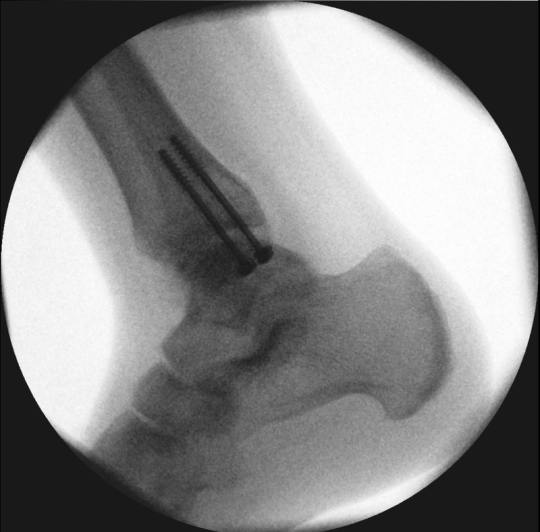

Offene ACT am Sprungbein (Talus) mit Abklappung des Innenknöchels (Osteotomie)

Röntgenbilder nach stufenlosem Verschrauben der Innenknöchel-Osteotomie